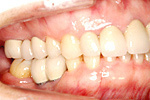

③ 下の顎・セラミッククラウン、ブリッジセット状態

④ 治療後。前から見た状態

④ 上の顎・ハイブリッドセラミックブリッジセット状態

⑤ 治療後・前から見た状態